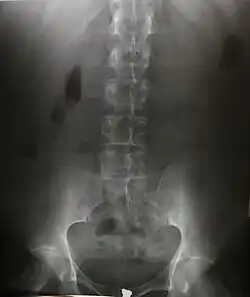

Radiografia é uma técnica de exame de imagem que utiliza raios X para ver um material cuja composição não é uniforme como o corpo humano. Um feixe heterogêneo de raios X é produzido por um gerador e projetado sobre um objeto. A densidade e a composição de cada área determina a quantidade de raios X absorvida. Os raios X que atravessam são capturados atrás do objeto por um detector (seja filme fotográfico ou detector digital). Produz-se então uma representação em duas dimensões de todas as estruturas superpostas.

O feixe de raios X, transmitido através do paciente, impressiona o filme radiográfico, o qual, uma vez revelado, proporciona uma imagem que permite distinguir estruturas e tecidos com propriedades diferenciadas. Durante o exame radiográfico os raios X interagem com os tecidos através do efeito fotoelétrico e Compton. Em relação à probabilidade de ocorrência destes efeitos, obtém-se imagens radiográficas que, mostram tonalidades de cor cinza bem diferenciadas; conforme a densidade, tudo o que está dentro do corpo surge em uma cor diferente numa radiografia.

Nos ossos, a radiografia acusa fraturas, tumores, distúrbios de crescimento e postura. Nos pulmões, pode proporcionar o diagnóstico da pneumonia ao câncer. Em casos de ferimento com armas de fogo, ela é capaz de localizar onde foi parar o projétil dentro do corpo. Para os dentistas, é um recurso fundamental para apontar as cáries. Na densitometria óssea, os raios X detectam a falta de mineral nos ossos e podem acusar a osteoporose, comum em mulheres após a menopausa. Na radiografia contrastada, é possível diferenciar tecidos com características bem similares, tais como os músculos e os vasos sangüíneos, através do uso de substâncias de elevado número atômico (iodo ou o suspensão de sulfato de bário). Ainda, o raio-X possibilitou o surgimento de exames como a tomografia axial computorizada (TAC) que, com ajuda do computador, é capaz de fornecer imagens em vários planos, de forma rápida e precisa, utilizando quantidades mínimas de radiação.